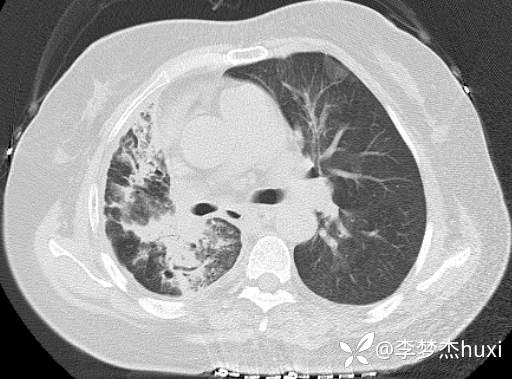

8.17胸部CT: